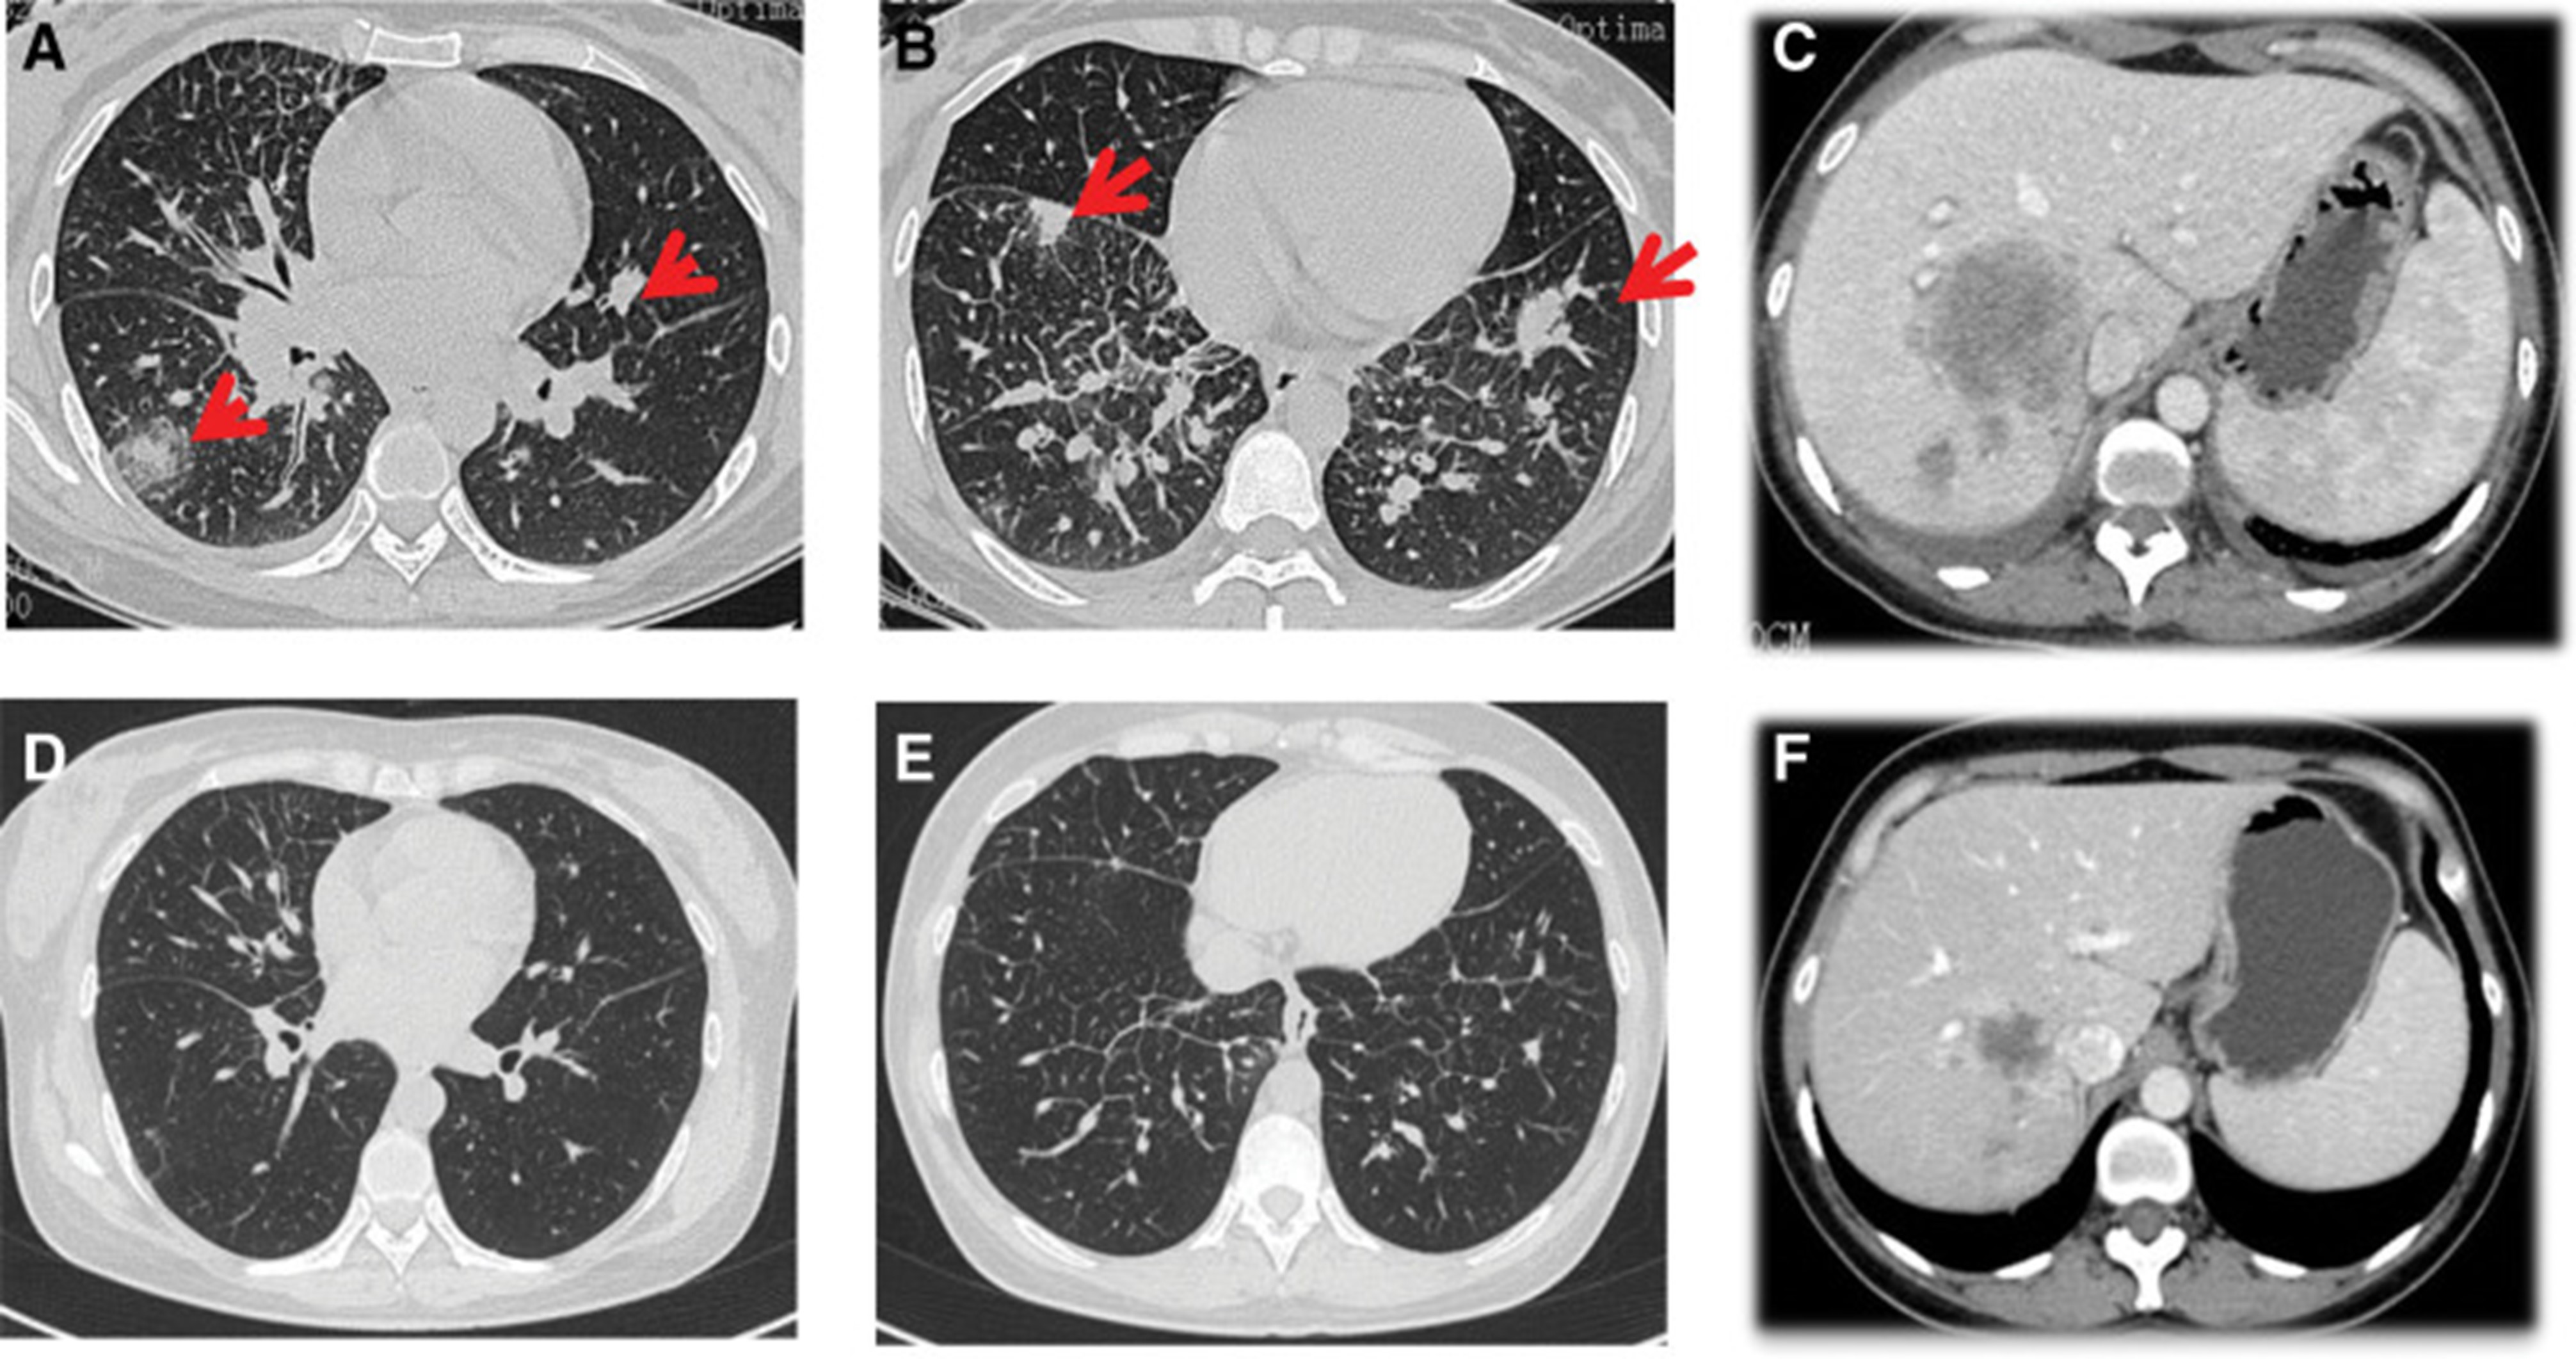

2020年4月,患者胸部CT示“双肺多发结节,纵隔及肺门多发肿大淋巴结;附着于肝右叶,略呈低密度肿块影”(图 1)。(图4A,4A、B)和腹部CT显示“肝脏多发肿块”(图1)。(图 4C)。骨扫描显示“身体多个部位的骨代谢异常增强”。2020年4月19日,对“右肝肿块和右锁骨上肿块”进行活检,病理指征(右肝肿块抽吸、右锁骨上肿块抽吸)为低分化腺癌。结合免疫组化结果,首先考虑的是肺腺癌转移。最终诊断为“IV期肺腺癌伴多发肝和骨转移”。基因检测显示“EML 4-ALK 融合,PD-L1 肿瘤阳性细胞数TPS 80%”(图 2)。(图1和和2)。

和 2020 年 6 月 (D-F).jpg)

图 4:2020 年 4 月 (A-C) 和 2020 年 6 月 (D-F) 的 CT 扫描。CT = 计算机断层扫描。

2020年5月1日,患者开始口服艾乐替尼靶向药物进行治疗,2020年6月25日复查,确定治疗效果为PR(部分有效)(根据RECIST1.1)显示肺病灶和肝转移灶明显减少(图1)。(图 3D-F)。2020 年 8 月 27 日复查确定治疗效果为疾病进展(PD, progressive disease),根据 RECIST1.1显示肝脏病变变大(图 1)(图 4A-D)。进行了第二次肝活检,随后的病理学显示“(肝)低分化癌,结合免疫组织化学分析考虑肺腺癌转移”。组织活检进行了第二轮基因检测,结果显示“BRAFV600E 14.79%,EML 4-ALK fusion 14.47%”(图 1)(图 5)。2020年9月20日,对患者我以为用恩沙替尼联合达拉非尼靶向治疗。治疗开始后,患者出现明显发热、寒战、乏力和厌食。期间患者左侧出现大量胸腔积液,胸腔积液中脱落细胞为“非典型细胞,考虑为腺癌”。随后,该患者接受了 1 次胸腔内铂输注。

和 2020 年 8 月.jpg)

图 5:2020 年 6 月(A 和 B)和 2020 年 8 月(C 和 D)的 CT 扫描。CT = 计算机断层扫描。

1个月后复查显示肺部和肝内病变进展(图1)。(图 6A-C)(根据RECIST1.1),她的抗肿瘤治疗改为“培姆曲塞加卡铂和贝伐单抗”的治疗一个周期。2020年12月至2021年1月,再次改变患者的治疗方案,这次改为“劳拉替尼联合达拉非尼”靶向治疗。使用 PD 联合胸部和腹部 CT 评估疗效(图 1)。(图 6D-F)(根据 RECIST1.1)。患者无法耐受化疗、靶向治疗、IO 治疗或任何其他积极的抗肿瘤治疗。这是因为患者的一般情况较差,包括发烧、腹痛和胆红素水平升高等症状。随后,给予患者静脉营养、镇痛等对症支持治疗。患者于 2021 年 2 月 4 日去世,总生存期(OS)为 10 个月。

和 2022 年 1 月 (D-F) 的 CT 扫描.jpg)

图 6:2020 年 11 月 (A-C) 和 2022 年 1 月 (D-F) 的 CT 扫描。CT = 计算机断层扫描。